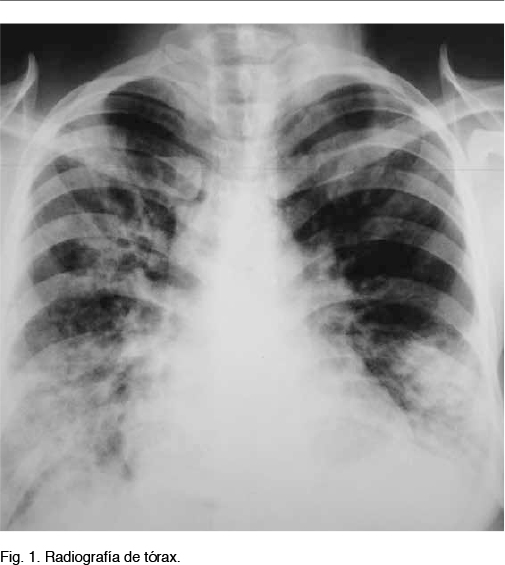

De la paraclínica: la radiografía de tórax muestra opacidad inhomogénea en 2/3 inferiores de hemitórax derecho y 1/3 inferior de hemitórax izquierdo, borramiento de fondo de saco costofrénico izquierdo. (Figura 1)